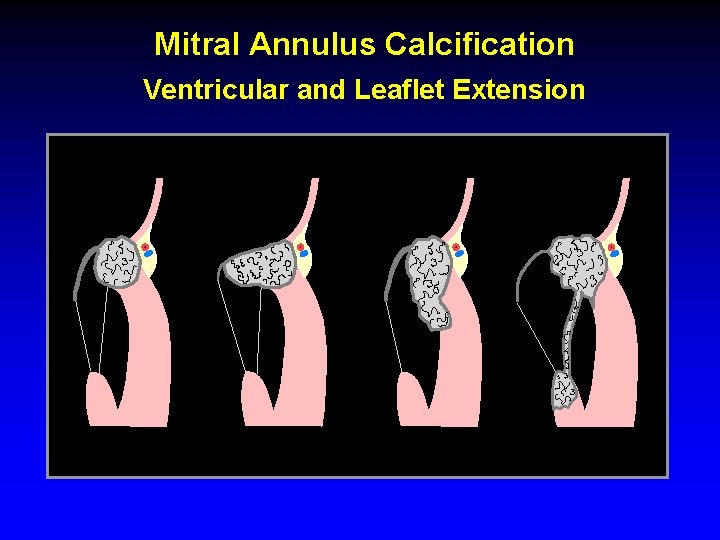

Mitral Annulus Calcification Ventricular and Leaflet Extension